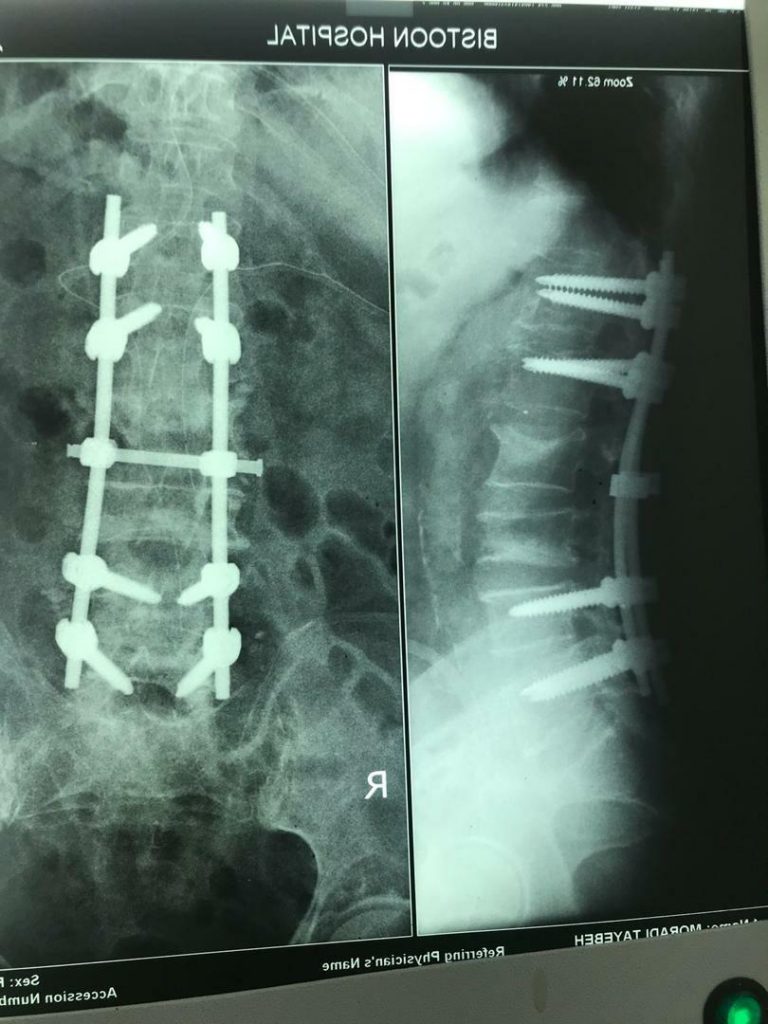

جراح ستون فقرات و دیسک کمری

4. بیماری‌های ستون فقرات

11. دیسک کمر و گردن